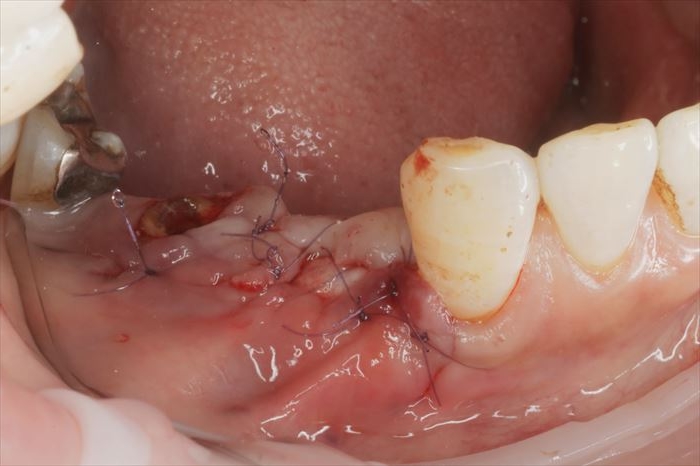

粘膜弁内部に減張切開を加えて伸展性を増やし、吸収性縫合糸で縫合しました。

撤去したブレードタイプインプラントです。